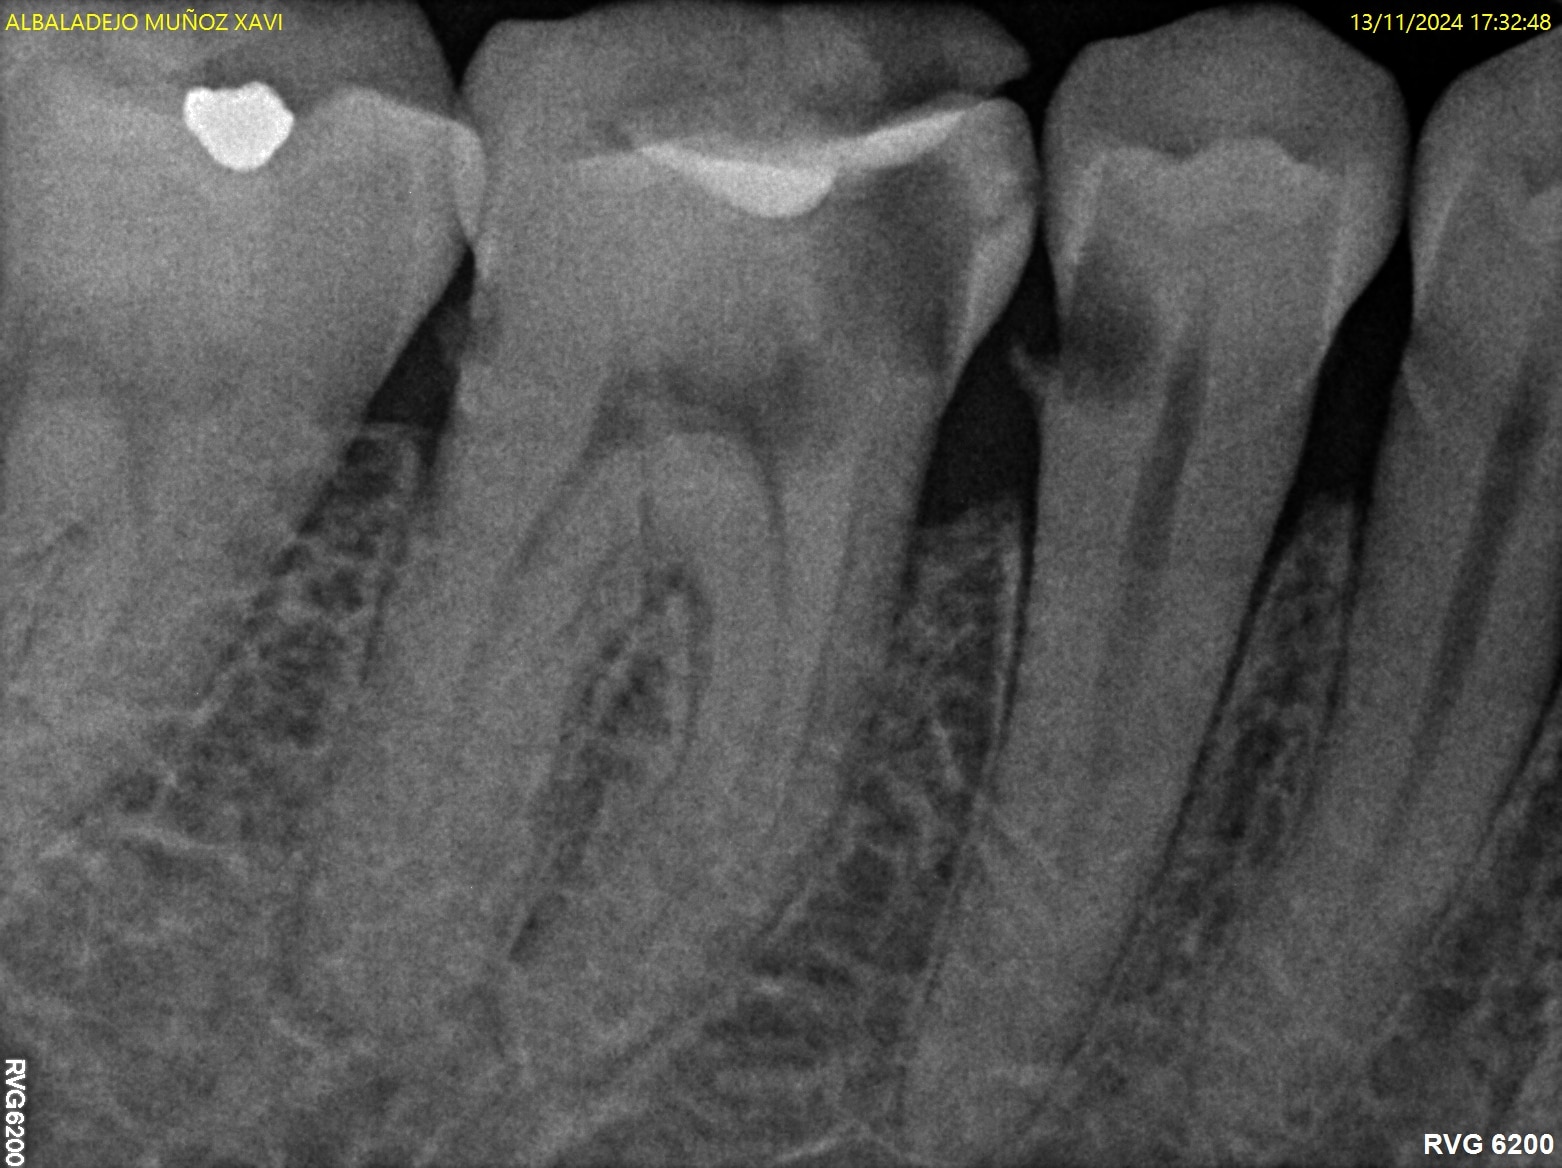

Paciente con presencia de caries extensas, se realiza tratamiento de conductos en 45-46 y posterior restauración con coronas cerámicas.